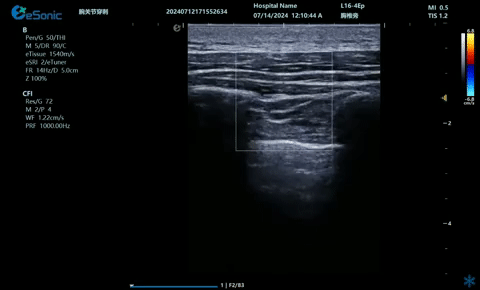

超声引导下蝶颚神经节阻滞术

大雁征-上颌动脉切面